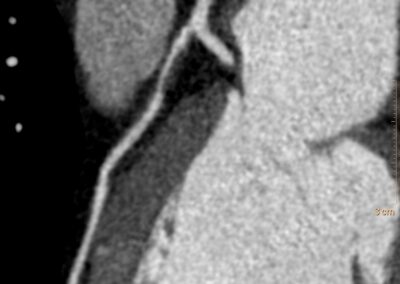

Τρισδιάστατη και δισδιάστατη απεικόνιση των στεφανιαίων αγγείων όπου διακρίνεται σημαντική στένωση λίγο μετά την έκφυσή του πρόσθιου κατιόντα κλάδου